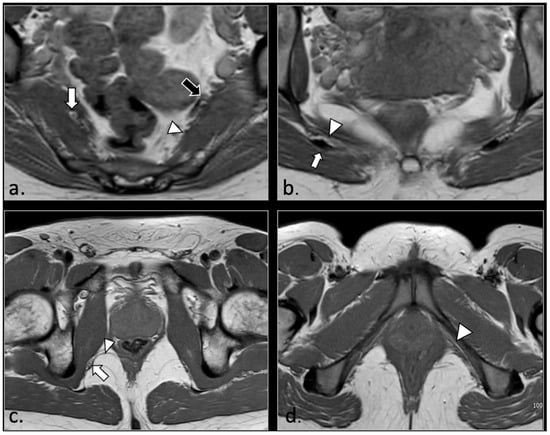

MRI in Chronic Pudendal Neuralgia: Diagnostic Criteria and Associated Pathologies

by Michele Gaeta, Sofia Turturici, Karol Galletta, Carmelo Geremia, Attilio Tuscano, Aurelio Gaeta, Marco Cavallaro, Salvatore Silipigni and Francesca Granata

Background/Objectives: Chronic pudendal neuralgia is a relatively rare condition in the general population, with an incidence of 1%. Although diagnosis of pudendal neuralgia is mainly clinical, Magnetic Resonance Imaging (MRI) is commonly performed to obtain further information. However, clear criteria and guidelines for MRI diagnosis and the clinical–radiological correlation are still not definite. Methods: We reviewed 81 patients with chronic pudendal neuralgia, studied by an MRI designed protocol for a pelvis and pelvic floor examination. A key element of the protocol was the use of a diffusion-weighted imaging (DWI) technique with echo planar imaging (EPI) sequence (b-values of 0, 100, and 600) for the neurographic evaluation of the nerve. Results: MRI examination revealed DWI abnormalities in 42/81 patients. Pudendal nerve abnormalities were unilateral in 33/42 patients and bilateral in 9/42. Moreover, in 23/42 patients, pathologies related to a high probability of neuropathy have been identified. Conclusions: This study highlights the role of pelvic MRI as a valuable imaging modality in the evaluation of patients with chronic pudendal neuralgia. In the study protocol we propose, an essential role is played by the DWI technique, which improves the visual definition of the pudendal nerve and related anatomical structures. By focusing on anatomical visualization and structured image interpretation, our work provides a practical imaging-oriented contribution to a field in which standardized MRI evaluation is still lacking. Full article